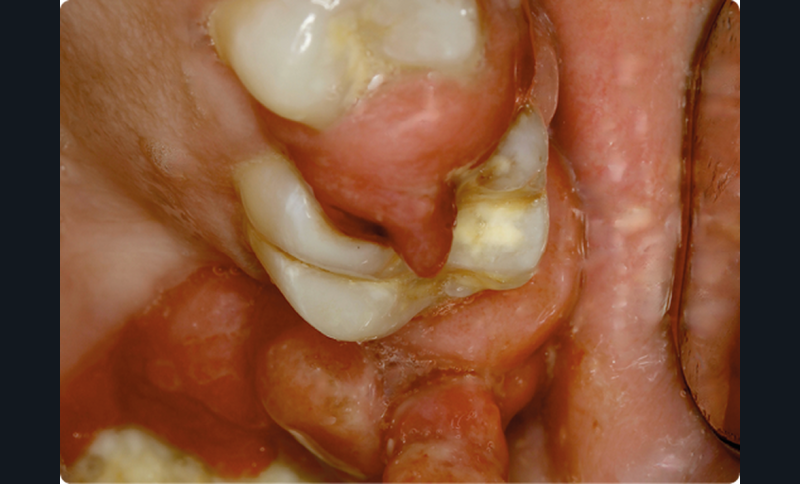

• On observait une hyperplasie gingivale intéressant les 4 régions molaire-prémolaire, avec des dents plus ou moins mobiles ; les secteurs antérieurs étaient épargnés. Cette hyperplasie gingivale était par endroits très volumineuse et prenait parfois l’aspect d’un granulome pyogénique.

• L’hyperplasie gingivale était revêtue par un épithélium malpighien kératinisé, irrégulier, comportant quelques ulcérations superficielles. Les crêtes épithéliales étaient par endroits discrètement hyperplasiques…